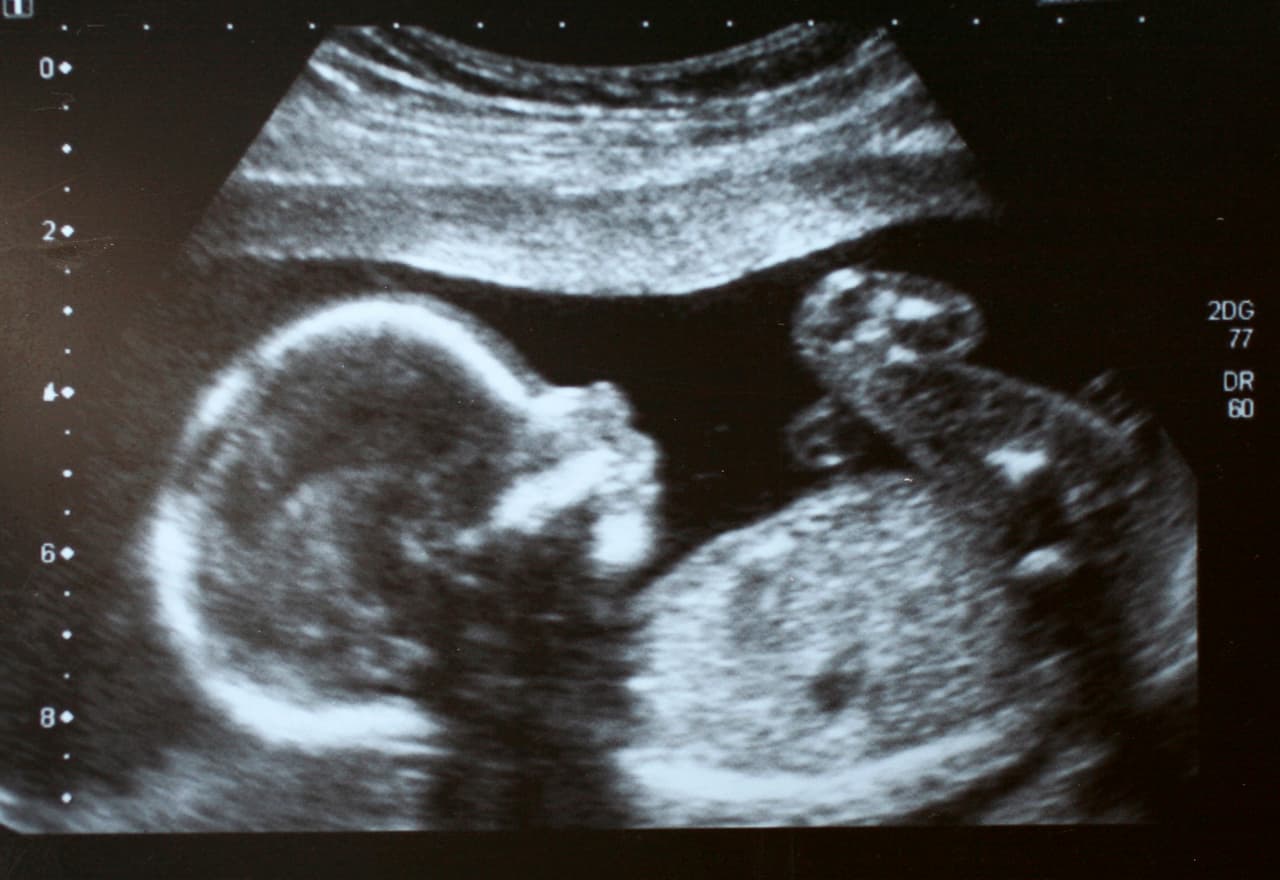

Solo basta mirarte para saber que darás el milagro de la vida y que esperas un bebé, pero no es posible saber a simple vista qué es lo que está sucediendo dentro tuyo. Mientras tu imaginas su carita, sus pequeñas manos y cómo serán sus ojos, dentro tuyo tu bebé está haciendo de las suyas. Aquí te cuento algunas cosas que no sabías del bebé que llevas dentro. ¡Te sorprenderás!

10 cosas que no sabías del bebé que estás esperando